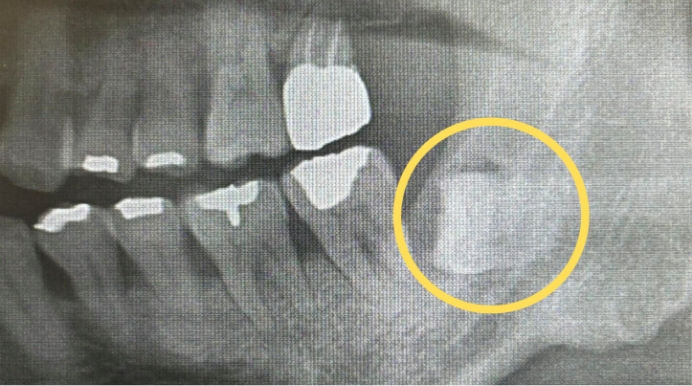

左上の親知らずを抜きたい

- 親知らずの生え方

- 斜めに生えている

- 抜歯時間

- 約30分

- 抜歯費用

- 約8,000円